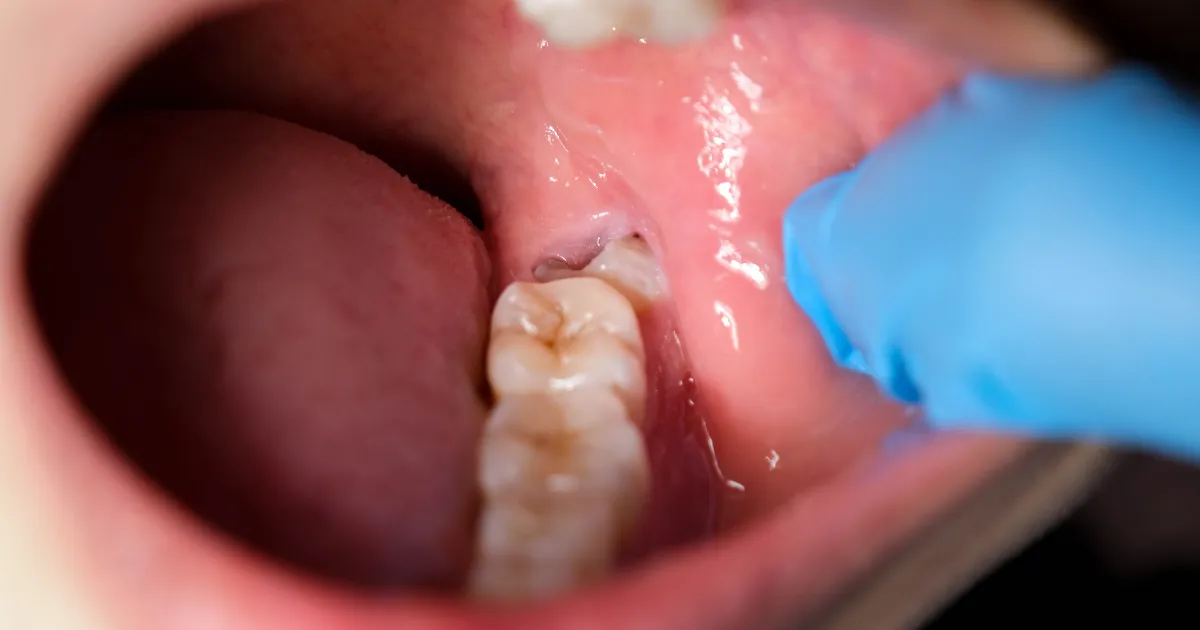

智歯周囲炎になっている

智歯周囲炎は、親知らずの周囲に細菌が感染し、歯肉や骨が炎症を起こす状態です。

この炎症が腫れや痛みを引き起こし、場合によっては顔全体に影響を及ぼすこともあります。